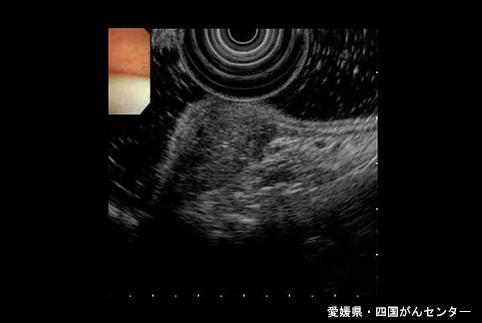

A case of ectopic pancreas in the stomach.

Ehime Pref., National Hospital Organization Shikoku Cabcer Center (Dr. 平崎)

[ Image ID:4973 ]

Tumor-like lesions/ectopic mucosa

Stomach/Angle

Ultrasonography

40 -